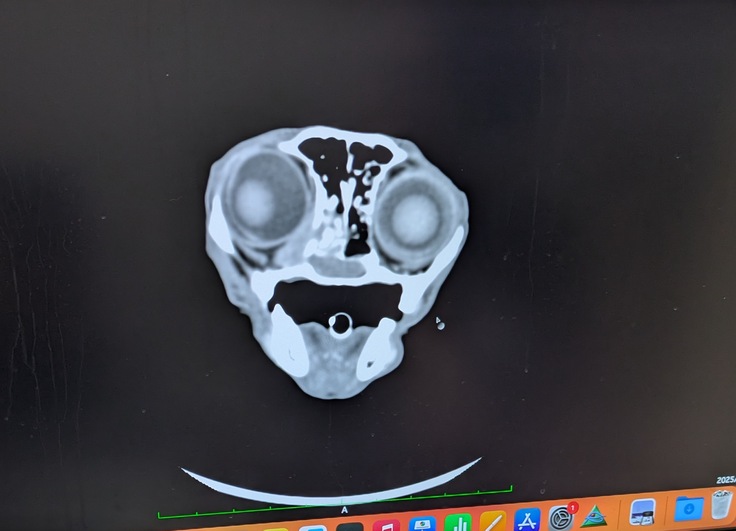

CTがある動物病院に予約を取ってもらい検査をしました。すると下記写真をご覧いただけると分かるかと思いますが左側鼻腔が腫瘍で鼻の気道をふさいでいました。目周りの骨も溶かし眼球部分まで腫瘍が侵食しています。

鼻腔内リンパ腫と診断を受けました。